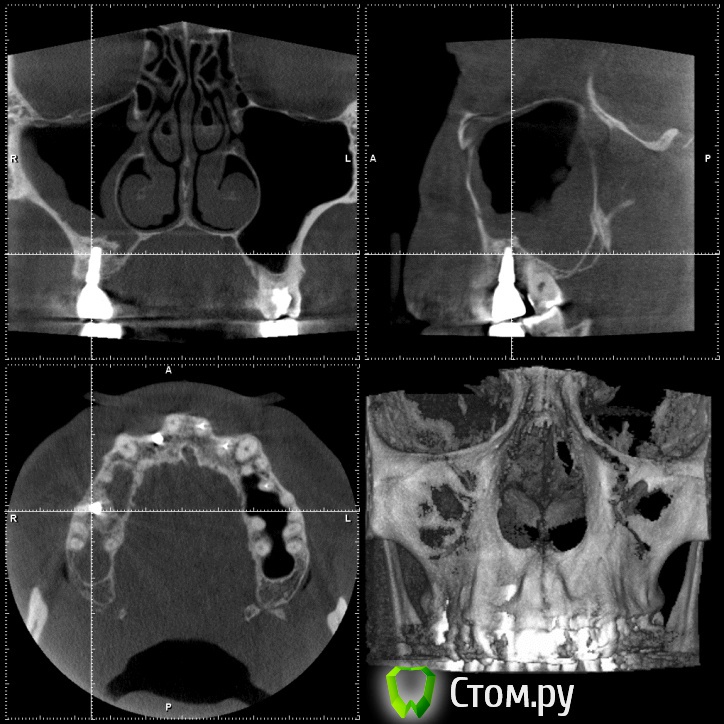

Britanez Опубликовано 2 июня, 2014 Поделиться Опубликовано 2 июня, 2014 В июле 2013 года были установлены 2 импланта 2 и 6 , 6ка с открытым синус лифтингом, в феврале 2014 установили коронки. Две недели назад обратил внимание на воспаление десны над обеими коронками,появился свищ над вторым имплатом и выделения белого цвета.Обратился к врачу, назначили пропить антибиотики 5 дней и сделать КТ. Антибиотики пропил над 6кой воспаление прошло ,над 2кой осталось,по результату КТ сказали что ушла кость и 2ку скорее всего придется удалять.Подскажите что можно сделать в данной ситуации, можно ли сохранить имплант?Ссылка на кт: http://my-files.ru/vbs51uСделал срезы кт: Ссылка на комментарий

Britanez Опубликовано 9 июня, 2014 Автор Поделиться Опубликовано 9 июня, 2014 Извините, что пишу в Вашей теме, просто хочу выразить сочувствие. Напишите потом, пожалуйста, как пойдут Ваши дела дальше, и что говорят врачи, почему произошло отторжение? А синус делали одновременно с постановкой обоих имплантов?? И ещё, выскажу просто мнение для администрации сайта и стоматологов, хотя сообщение наверняка удалят. Меня удивляет, для чего тогда сделана ветка для вопросов пациентов, когда за несколько дней ни один уважаемый стоматолог не заглянул и ничего не написал... После этого задумаешься, стоит ли размещать свои снимки, фотографии и проблемы..... Отвечу здесь если кому то интересно.Синус на 6ку делали одновременно с постановкой двух имплантов.Врачи говорят, что воспаление пошло из-за того что верхний край импланта вышел за пределы костной ткани (на втором снимке видно) и при нагрузке началось воспаление, хотя имплант стоял очень крепко ,открутить не смогли, выпиливали, чем то типа круглой коронки.Если здесь кто нибудь из врачей объяснил (подтвердил) причину воспаления, был бы очень признателен. Ссылка на комментарий

Bier Опубликовано 9 июня, 2014 Поделиться Опубликовано 9 июня, 2014 Имплантат частично стоял не в кости и кости судя по в ему было очень мало еще до имплантации. Ссылка на комментарий